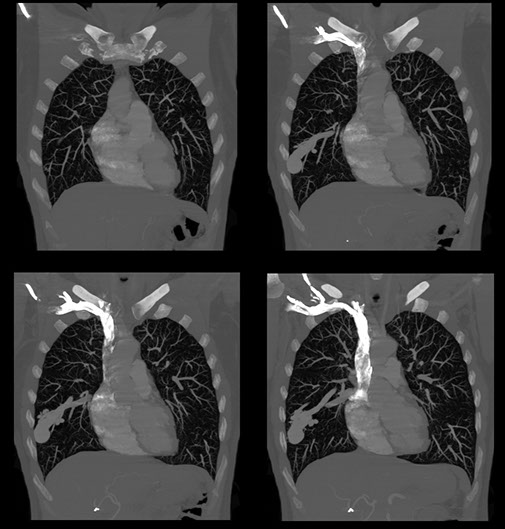

This patient had a large cerebral haemorrhage, from an arteriovenous malformation fed by branches of the internal carotid and vertebral arteries.

Selective catherization of feeding vessels revealed a small aneurysm which presumably is the cause of the haemorrhage, as indicated by the green arrow.

The aneurysm was occluded by a minute amount of glue, which can be seen on the bottom left of the image.

This patient was known to have a vascular cerebral lesion. The patient saw a neurosurgeon operating on a similar patient on TV. She then decided to consult the same surgeon who successfully removed the arteriovenous malformation. Pre-operative embolisation of the arteriovenous malformation made the operation easier and the lesion was excised in 4 hours . Post embolisation images are seen in the top right image.

Embolisation of the branches of the posterior cerebral artery. Note the reduced circulation of the left cerebral hemisphere.

We see the meningeal artery also supplying the lesion

Images showing the location of multiple coils and marked reduction in the blood supply from the internal carotid artery. This procedure allowed the surgical removal of the AVM to be safer and much quicker, the lesion was removed in 4 hours.